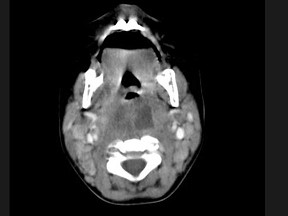

18.10个月大的婴儿,发热,曾患中耳炎,CT扫描如图所示,请选择正确的描述或诊断 ( )![]() ![]() ![]() |

| 正确答案:ABCD |